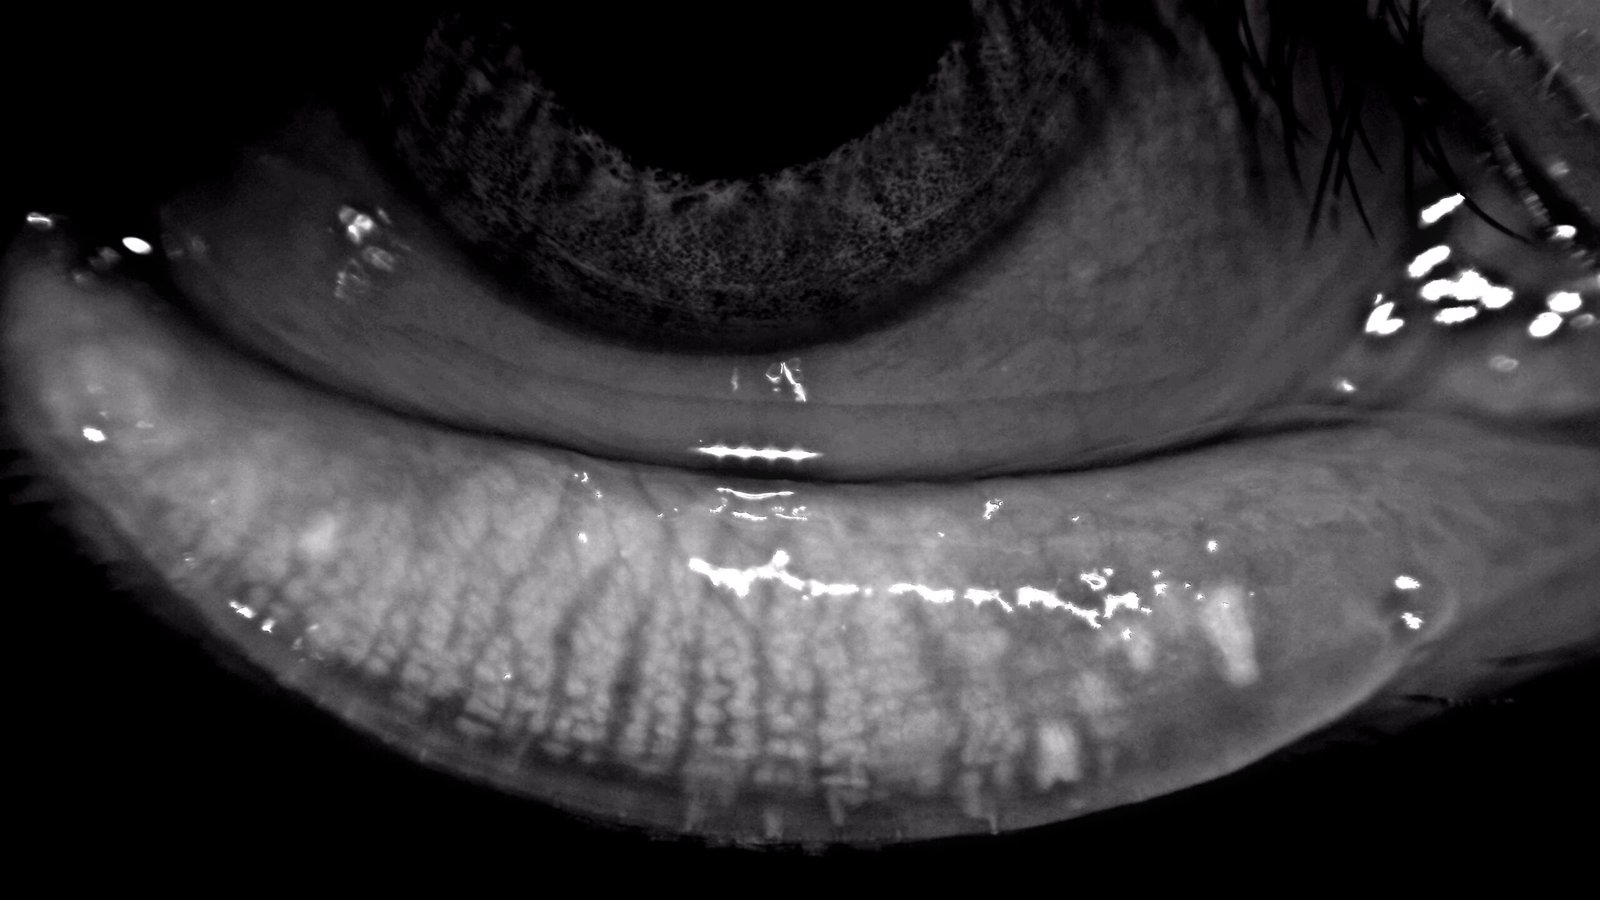

High-Resolution Imaging with Clinical Precision

8MP Camera with Precision Optics for High-Detail Visualization

3-Minute Dry Eye Exam: Meibography, Interferometry, TMH, NIBUT

Meibography, NIBUT, TMH, Redness, Interferometry, Blink, Demodex, Pupillometry